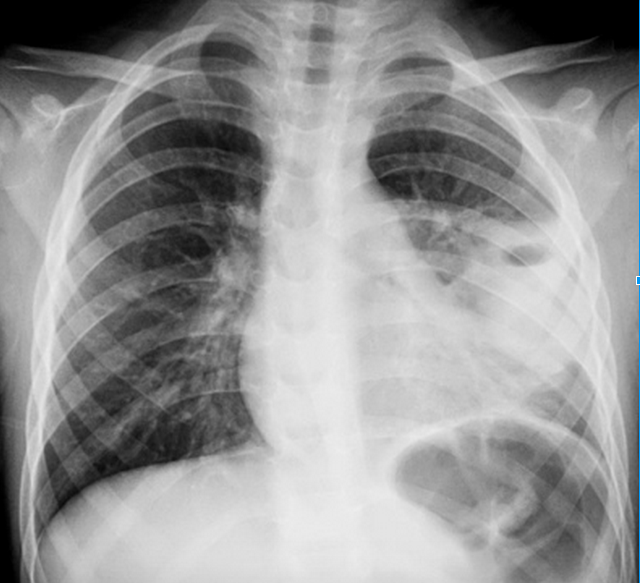

From Radiopaedia: (https://radiopaedia.org/articles/chronic-obstructive-pulmonary-disease-1)